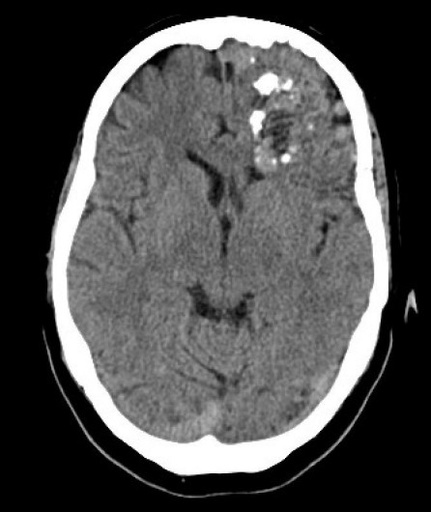

Lésions vasculaires (MAV-fistules-Moya-Moya) cérébrales et médullaires

BONNET T. - ULB

DES SPECIALITE

Année académique 2023-2024

Nerveux Vasculaire DES SPECIALITE Cerveau